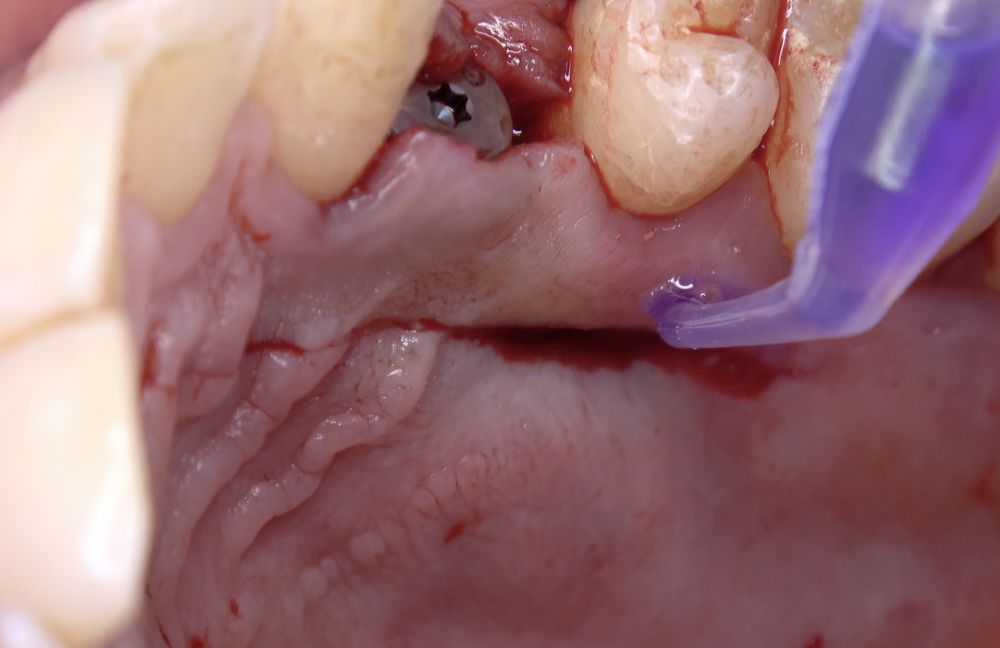

Métodos: Se reportan los resultados preliminares de un estudio clínico aleatorizado. 20 pacientes fueron divididos en dos grupos: uno en el que se utilizó sutura (grupo control) y otro donde se aplicó un adhesivo tisular a base de cianoacrilato (grupo test). Se compararon variables como el dolor postoperatorio, la cicatrización, el consumo de analgésicos y la disposición de los pacientes a someterse a otro procedimiento similar.

La cirugía plástica periodontal es el tratamiento de elección en casos de recesiones gingivales y defectos mucogingivales1,2. Actualmente, los injertos de tejido conectivo (ITC) son considerados el gold standard para la reconstrucción del tejido blando, debido a la estabilidad y biocompatibilidad que ofrecen a largo plazo2. Para la obtención del ITC, la técnica más común es la descrita por Zucchelli y cols.3, consistente en recolectar un injerto gingival libre que luego será desepitelizado extraoralmente. Existen otras alternativas en la obtención de este tipo de injertos, como la técnica en única incisión4, destinadas a minimizar la morbilidad en la zona donante. Sin embargo, el uso de ITC siempre implicará un área donante, generalmente palatina, aumentando la complejidad del procedimiento y las molestias del paciente durante el postoperatorio que, durante el proceso de cicatrización, podrían acarrear complicaciones como sangrado, dolor, infección o necrosis, mayormente relacionadas con la incapacidad de formar un coágulo sanguíneo estable5-8. Además de la sutura, se han empleado diversos agentes hemostáticos y cicatrizantes para lograr esta estabilización, como los adhesivos a base de cianoacrilato8. Entre las propiedades de estos adhesivos tisulares destacan su excelente capacidad hemostática, rápida adhesión a los tejidos y posibles cualidades bacteriostáticas8. Estudios previos indican que el uso de estos agentes en la cicatrización de la zona donante palatina tras la obtención de ITC con diferentes técnicas es prometedora9,10; sin embargo, la literatura sobre la cicatrización y respuesta del tejido en la zona donante palatina tras la obtención de injertos de tejido conectivo en incisión única aún es escasa. Por lo tanto, el objetivo del presente estudio fue evaluar y comparar el uso de sutura y cianoacrilato en la zona donante palatina tras la obtención de ITC.